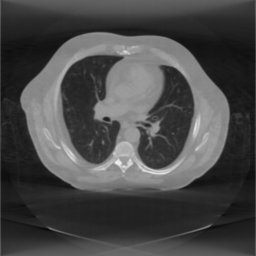

The pipeline outputs a reconstructed volme in MHD format. A slice from the reconstructed volume (on the sample dataset) is shown in the figure below.

fdkRamp.jpg